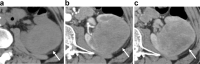

Granulomatosis with polyangiitis (GPA) manifests as necrotizing granulomatous inflammatory masses in the nasal cavity, paranasal sinuses, and lungs. However, a mass in the kidney is extremely rare. We herein report a case of GPA that presented as a solitary mass in the left kidney. The patient was a man in his 60s. A 2.5-cm solitary mass was incidentally discovered in the left kidney at another hospital and was followed-up. Eight months later, the mass had enlarged, and the patient visited our hospital for further examination and treatment. The mass was hypovascular, with unclear margins on contrast-enhanced computed tomography (CT). The signal of the mass was nonuniform and iso- to slightly hypo-intense on T2-weighted and diffusion-weighted magnetic resonance imaging (MRI). Enlarged para-aortic lymph nodes were also detected on the CT and MRI. Based on imaging, malignant tumors were suspected, and nephrectomy was performed. The pathological diagnosis was GPA. We performed a literature review of this rare renal manifestation and present a summary of reported imaging findings. If a hypovascular renal mass with an unclear margin can be found in those with GPA, unnecessary operations may be avoided by actively promoting renal biopsy.